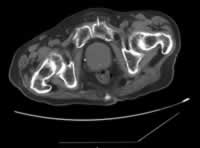

患者1年前从楼梯上不慎摔倒,半月后病人搬动花盆后出现腰背部疼痛。就诊于当地医院,胸腰椎X线片示:T12压缩性骨折。服中药治疗,服药6天后出现食欲下降,第14天起出现恶心呕吐,为胃内容物,无呕血。再次就诊,腹部 CT示胆囊炎、胆石症。胃镜示浅表性胃炎伴胆汁反流。肝功能、肿瘤指标、血尿淀粉酶均未见异常,血钙2.41 mmol/L。予以“奥美拉唑、头孢氧哌唑(先锋必)、甲氧氯普胺(胃复安)”等治疗后病情无明显改善,遂入院进一步诊治。查血常规示贫血(RBC 2.19×1012/L, Hb 74 g/L)。腰椎MRI示T12、 L2、 L3椎体压缩性骨折,以L3为甚,伴椎管狭窄,L4-5椎间盘突出。免疫球蛋白IgA 1060 mg/dl升高(↑)IgM 44.50 mg/dl降低(↓)。血沉(ESR)114 mm/h↑。 经氨基酸、脂肪乳营养支持,叶酸等纠正贫血后10天患者病情好转出院。出院诊断为“胸腰椎骨折,高免疫球蛋白血症(IgA)。”出院后病人病情稳定,无恶心呕吐,无腰背疼痛,能进行轻度体力活动。直至本次入院前2个月,病人再次出现腰部疼痛,呈进行性加重,行物理治疗疗效不佳,后又出现恶心呕吐不能进食。于两周前入住当地医院查血钙3.76 mmol/L,给予降钙治疗、营养支持、对症治疗后仍有呕吐腰痛,故收住我科进一步诊治。

入院查体 T 37.5 ℃,BP 150/80 mmHg,贫血貌,皮肤无黄染、皮疹和出血点。颈下、腋下及腹股沟可触及肿大淋巴结 ......